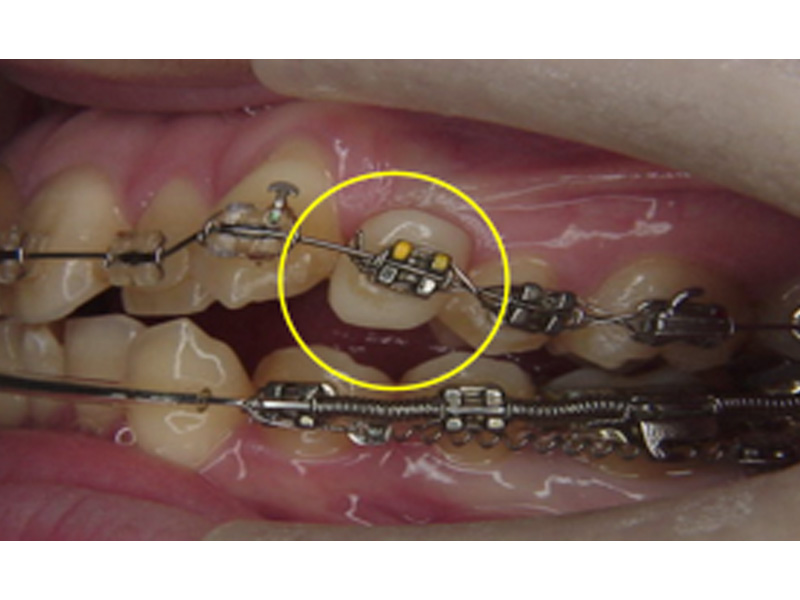

そのような場合、その部分の矯正装置に人工歯を組み込むことができます。飾りなので、咬むのに使うのは厳禁ですが、見た目は十分にカバーされます。唇側・舌側のいずれでも、可能です。